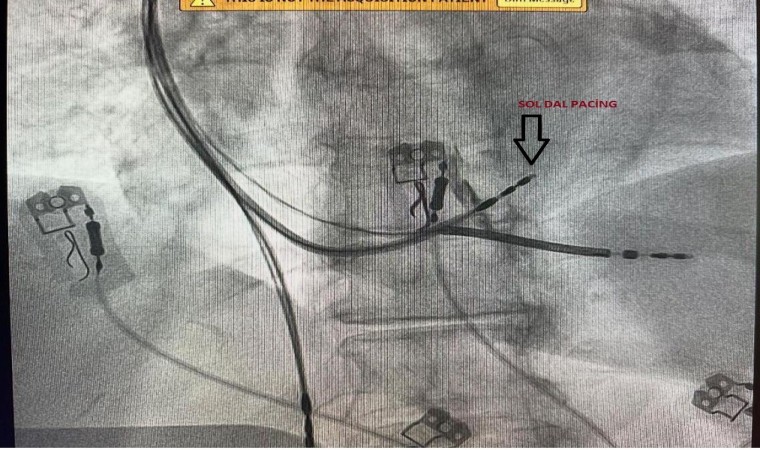

Elazığ Fethi Sekin Şehir Hastanesi’nde Kardiyoloji Uzman Dr. Öğretim Üyesi Zeki Çetinkaya ve Kardiyoloji Uzmanı Mehmet Ali Gelen tarafından ilk defa ‘Sol Dal Pacing’ sistemi ile kalp pili ameliyatı yapıldı.

Elazığ Fethi Sekin Şehir Hastanesi, sağlık alanında ki başarılı çalışmalara bir yenisi daha ekledi. Türkiye’de sadece belirli merkezlerde yapılan ‘Sol Dal Pacing’ ameliyatı Fethi Sekin Şehir Hastanesi’nde 3 hastanın ameliyat edilmesiyle başladı. Hastanede görevli Kardiyoloji Uzmanları Dr. Öğretim Üyesi Zeki Çetinkaya ve Uzm. Dr. Mehmet Ali Gelen, aldıkları eğitimin ardından hastanede ‘Sol Dal Pacing’ yöntemi ile kapalı pil ameliyatını başarılı bir şekilde gerçekleştirdi. Kalbin içerisindeki çarpıntıların tespit edilmesi ve ardından ablasyon ile teknik tedavi uygulanan ameliyat yöntemi, daha önceden yapılan kalp ameliyatlarının nefes darlığı ve kalp yetmezliği oluşturmasını ortadan kaldırıyor. Başarılı ameliyatların ardından bilgiler veren doktorlar, dünyada yeni uygulanan Türkiye’de ise belirli merkezlerde yapılan ameliyat yöntemi ile Fethi Sekin Şehir Hastanesi’nin bu alanda öncü olacağını belirtti.

Türkiye’de belirli merkezlerde yapılan fakat Elazığ’da bir ilki gerçekleştirdiklerini aktaran Dr. Öğretim Üyesi Zeki Çetinkaya, “Sol Dal Pacing yöntemi ile 3 hastamızı ameliyat ettik. Bundan sonra da bu şekilde devam edeceğiz. Bu ameliyatın özelliği kalbin doğal ileti sistemi üzerine pil kablosunu yerleştirdikten sonra kalbin sağ ve sol karıncıklarının uyumlu şekilde çalışmasını sağlıyoruz. Diğer normal taktığımız pillerde ise öncelikle kalbin sağ karıncık kısmı uyarılıyor, sonra sol karıncık kısmı geç uyarılıyordu. Bu şekilde 10 hastanın 2’sinde kalp yetmezliği ve nefes darlığı olabiliyordu. Bu pil yöntemi, dünyada yeni uygulanıyor. Hastalarımız bu ameliyat yöntemi ile daha fayda görmektedir. Özellikle ritim bozukluğu ve nefes darlığı olan hastalarda bu işlemleri başarılı şekilde uygulamaktayız. Bu ameliyat, Ankara, İstanbul ve belirli merkezlerde yapılmaktadır. Burada ise ilk defa yaptık ve başarılı olduk. Katkılarından dolayı Prof. Dr. Uğur Canpolat hocamıza da teşekkür ederiz. Buranın ilerleyen dönemlerde bölge merkezi olma ihtimali de çok yüksek. Bu ameliyatın özelliği doğal ileti sistemi üzerine kablo koyularak kalbin senkron şeklinde yani iki ventürkülün de aynı anda kasılmasını sağlıyoruz. Bu şekilde hastalarda nefes darlığı daha az oluyor. Bu pil yöntemi takıldığında hastalarımız daha konforlu ve nefes darlığı olmayacak şekilde yaşamlarını devam ettirebilirler” dedi.

Kardiyoloji Uzmanı Dr. Mehmet Ali Gelen ise “Normalde kalp yetersizliği ve ritim bozukluğu olan hastalarımızda kalp pili, sık tercih edilen bir yöntemdir. Özellikle dünyada yeni yapılan ve Türkiye’de bazı merkezler de yapılan bu yeni yöntemi bizde Elazığ’a kazandırmak istedik ve 3 hastamızın ameliyatlarını başarılı bir şekilde gerçekleştirdik. Özellikle kalbin ana ileti sistemine pacing yaparak bir pil ablasyonu yapıldı. Bu hastalarda kalp yetersizliğini riskini azaltır ve yaşam konforunu arttırır. Aynı zamanda hastaların ilaç tedavisi yanıtını da arttırabilen bir yöntemdir. Önceden hastalar, bu tarz özellikli işlemleri yaptırmak için Ankara, İstanbul, İzmir ve Bursa gibi şehirlere gitmeleri gerekiyordu fakat biz bu sol dal pacing ameliyatını başarılı bir şekilde yaptık. Bundan sonra bölge ve Elazığ’da ki tüm hastalar, farklı bir şehre gitmeye gerek duymadan Fethi Sekin Şehir Hastanesi’nde ameliyatlarını olabilecekler” ifadelerini kullandı.